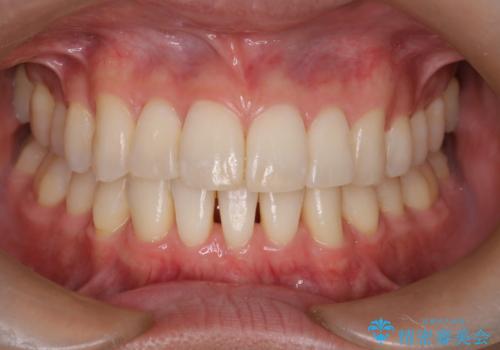

前歯の重なりとガタガタをマウスピースで改善した症例

初診時の歯並びの状態としては、上下ともに前歯部の中等度のがたつきがあり、上の前歯が重なっている状態でした。

また元々下の前歯は1本少なく、歯の本数が少ないことを前提とした矯正治療を行いました。

抜歯は必要なく、マウスピース矯正にて治療を行っています。

見た目、嚙み合わせ及び、治療期間や施術内容に大変ご満足いただきました。